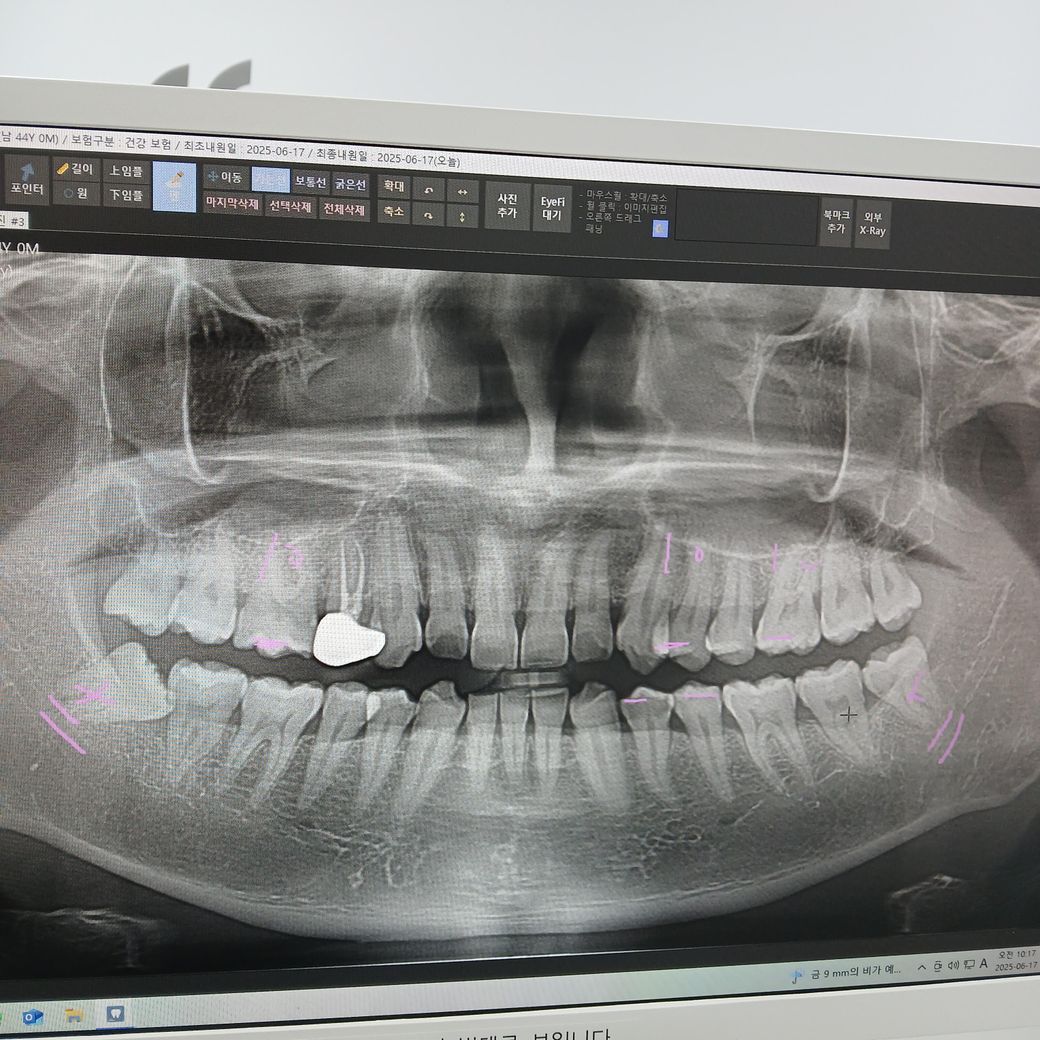

(이번에 찍은 엑스레이)

• 3번 째 사진